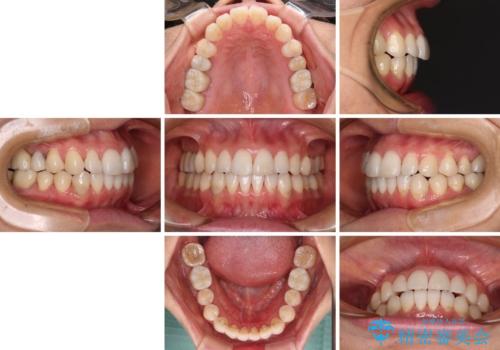

インビザライン・ライトによる矯正治療であったので、時間をかけずに治療を終えることができました。

口を開ける度に目立っていた銀歯もセラミックで自然な口元の印象となりました。